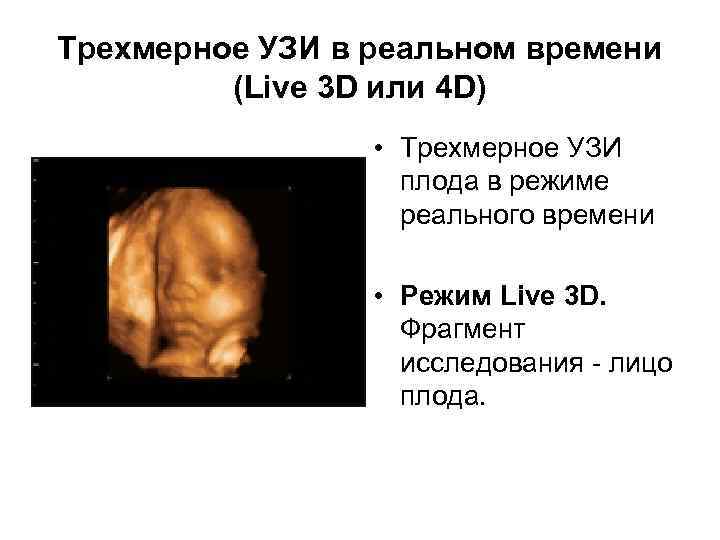

Трехмерное УЗИ в реальном времени (Live 3 D или 4 D) • Трехмерное УЗИ плода в режиме реального времени • Режим Live 3 D. Фрагмент исследования - лицо плода.

Трехмерное УЗИ в реальном времени (Live 3 D или 4 D) • Трехмерное УЗИ плода в режиме реального времени • Режим Live 3 D. Фрагмент исследования - лицо плода.